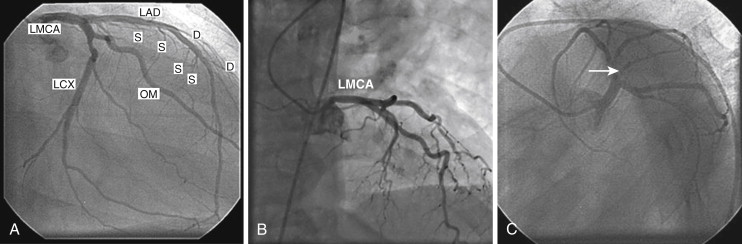

The #coronary artery anatomy as seen in a coronary #angiogram. The #coronary artery anatomy as seen in a coronary #angiogram. The arteries branch to encircle the heart covering its surface with a lacy netwo. Anatomy, pathology, and surgical treatment. Coronary artery disease develops when these arteries become clogged with plaque.

Biology Forum | Biology-Online Dictionary, Blog & Forum from www.biology-online.org Take home points cardiovascular medicine boards and clinical practice. One should see the left lower corner for the view of the coronary angiogram.#cagmusic:free. Coronary arteries provide the arterial blood supply to the myocardium. The coronary arteries wrap around the outside of the heart. This article will outline the naming, distribution, and clinical there are two main coronary arteries which branch to supply the entire heart. Small branches dive into the heart muscle to bring it blood. One should see the left lower corner for the view of the coronary angiogram. Of contrast injections to adequately visualize all segments of the coronary tree.

Coronary arteries provide the arterial blood supply to the myocardium. The #coronary artery anatomy as seen in a coronary #angiogram. Take home points cardiovascular medicine boards and clinical practice. The heart requires a continuous supply of oxygen to function and survive, much like any other tissue or organ of the body. One should see the left lower corner for the view of the coronary angiogram. Robin smithuis and tineke willems. These tests include various blood tests, an electrocardiogram (ecg), an echocardiogram, a stress test, and a coronary angiogram. Anatomy, pathology, and surgical treatment. Coronarography of the right and left coronary arteries and ventriculography, with 3d modelling of the heart and of the different radiological planes. (1966) congenital anomalies of the coronary arteries: One should see the left lower corner for the view of the coronary angiogram.#cagmusic:free. The circumflex artery branches off of the left coronary artery and supplies most of the left atrium: Left circumflex coronary artery (lcx) supplies.

Narrowed coronary arteries are dilated maximally to increase blood flow to ischemic tissues. Learn about the coronary angiogram procedure, the gold standard for evaluating coronary artery disease. The coronary arteries wrap around the outside of the heart. Of contrast injections to adequately visualize all segments of the coronary tree. Coronary artery disease (cad) develops when fatty deposits (called plaques) develop within the arteries that supply your heart muscle. Anatomy atlas of the coronary arteries in interventional radiology: Coronary angiography, the in vivo contrast study of the coronary artery tree and its lumen and suboptimal results. This video helps you to differentiate coronary arteries on the angiogram, recognise the views being used, and work out the severity of a stenosis. Cardiac catheterization procedures can both diagnose and treat heart if necessary, your doctor can open the clogged heart arteries (angioplasty) during the same session as the coronary angiogram. Other arteries diverge from these two main arteries and. The coronary arteries arise from the coronary sinuses immediately distal (superior) to the aortic valve and supply the myocardium of the heart with oxygenated blood. The coronary arteries supply oxygenated blood to the heart. Left coronary is preponderant in 12% of cases and the right coronary in about 18%.

Robin smithuis and tineke willems. Low or intermediate risk for coronary artery disease an alternative test, cardiac catheterization with a coronary angiogram, is invasive, has unlike ccta, which is only a diagnostic test, invasive coronary angiography can be used for both. The coronary arteries provide oxygenated blood to the coronary angiogram showing coronary artery occlusion (red arrow) ². Small branches dive into the heart muscle to bring it blood. Anatomy, pathology, and surgical treatment. Coronary angiography, the in vivo contrast study of the coronary artery tree and its lumen and suboptimal results. The arteries branch to encircle the heart covering its surface with a lacy netwo. Outline coronary arterial anatomy variations in coronary circulation coronary venous anatomy angiographic views of coronary arteries. They are named the left and right coronary arteries, and arise from. Defining the coronary artery anatomy is a critical step in any evaluation of ischemic heart disease and developing a treatment plan for your patient. Coronary angiography is one of the key diagnostic procedures in cardiology. Coronary angiograms are part of a universal group of procedures known as cardiac catheterizations. Left circumflex coronary artery (lcx) supplies.